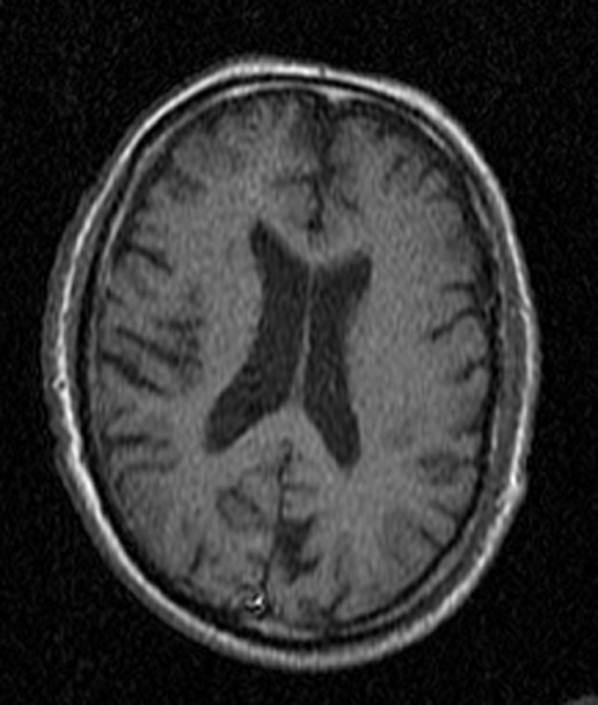

CT: Brain Atrophy

10 Years-Normal Gyri             65 Years-Enlarged Gyri